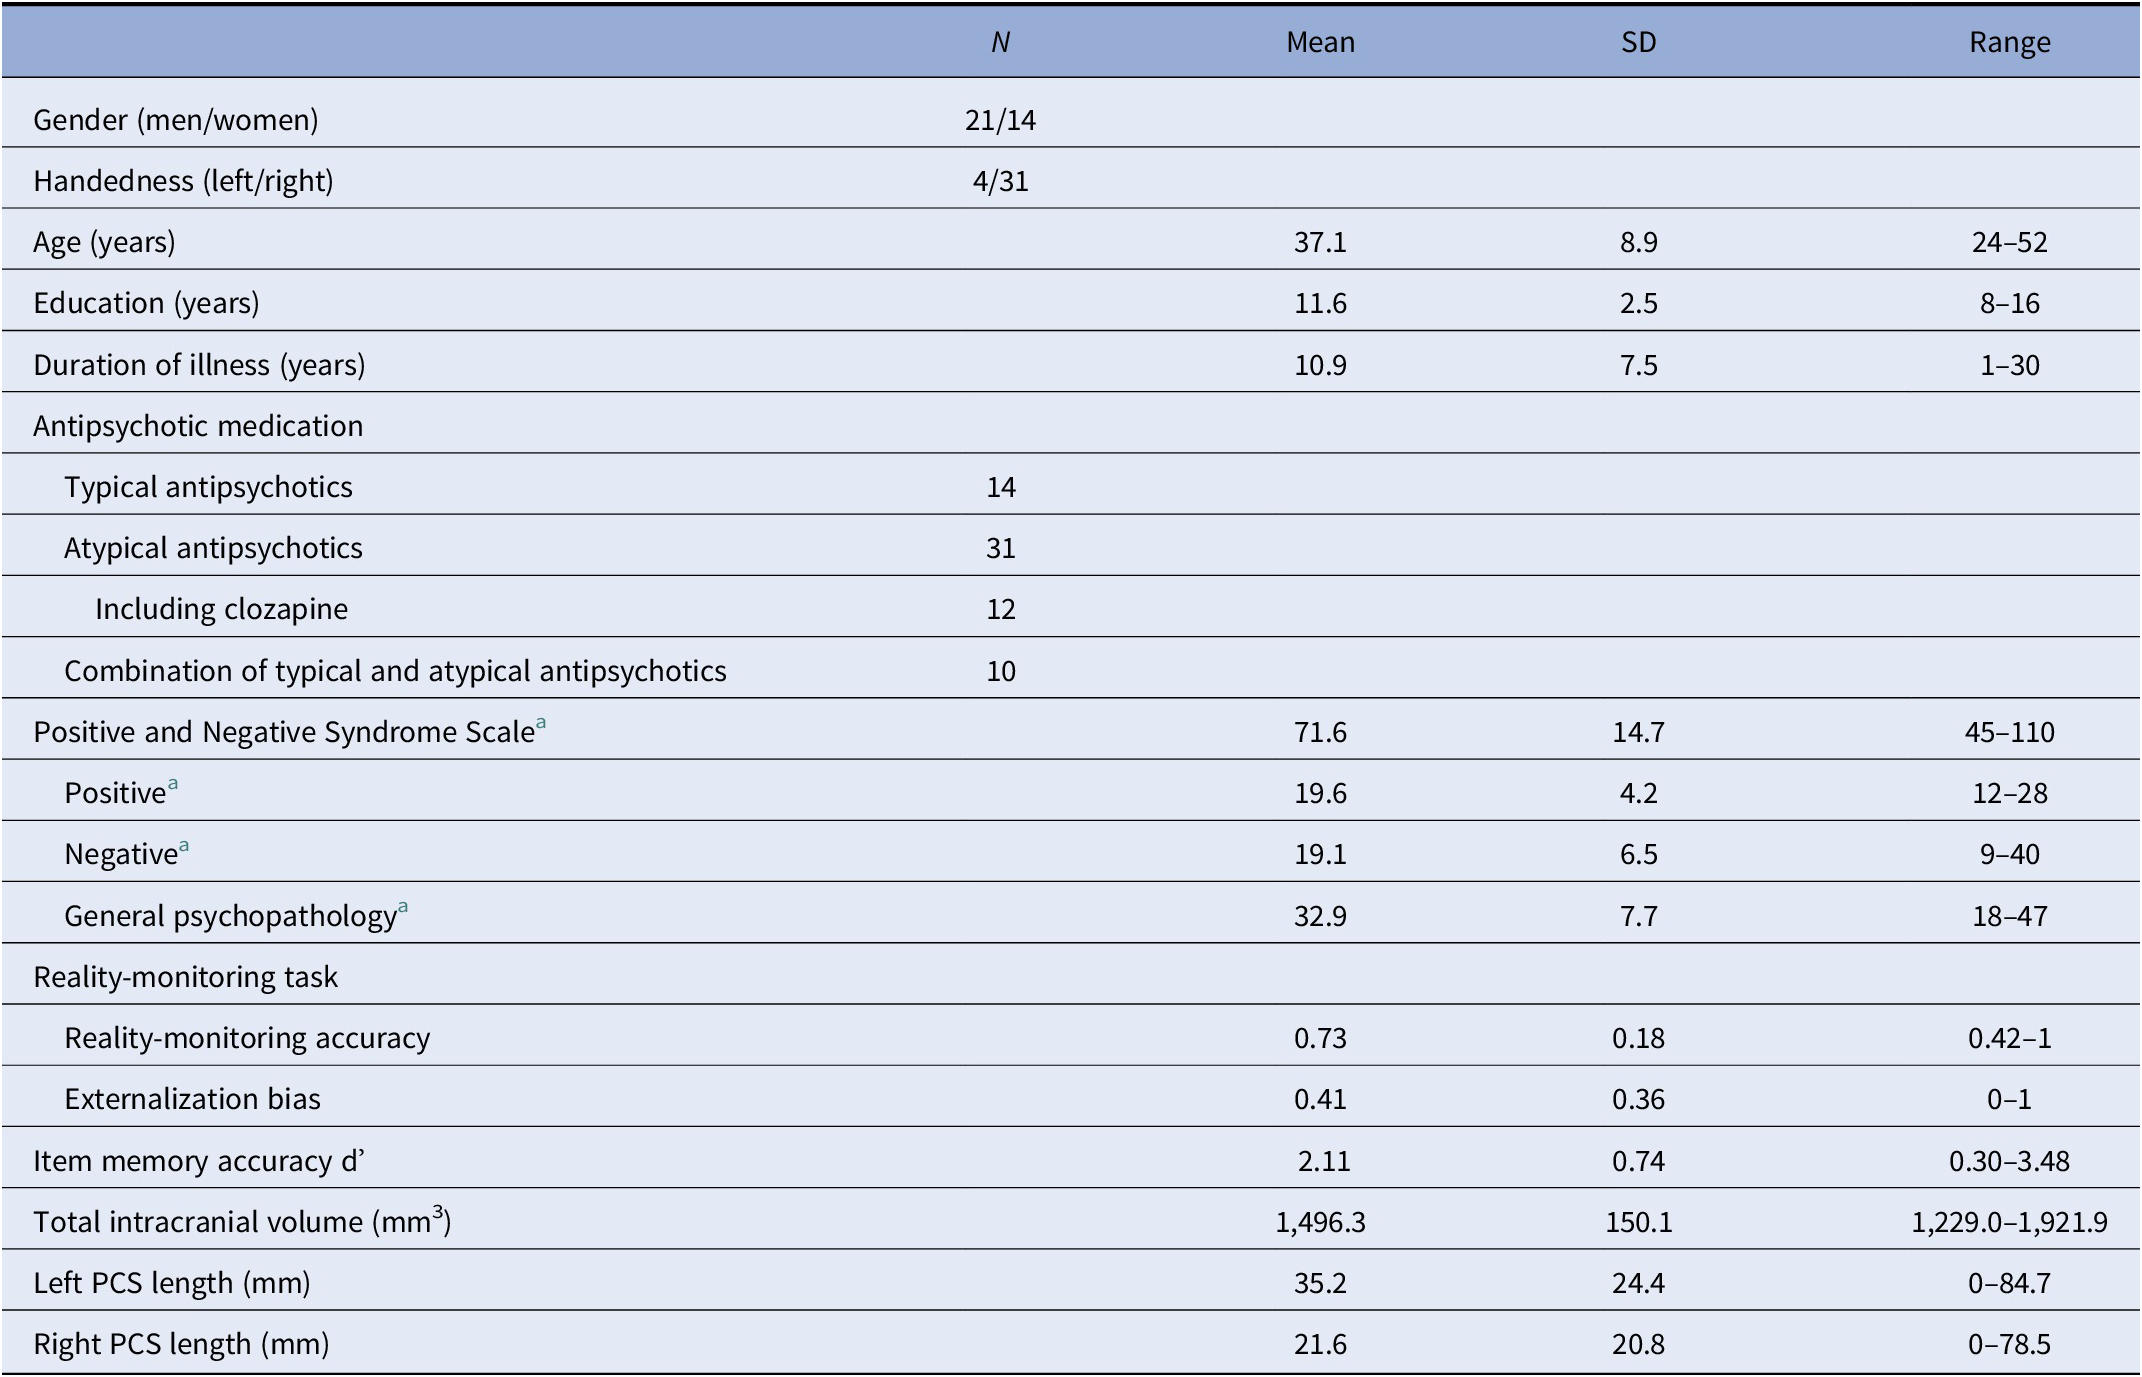

Table 1. Summary of demographic, clinical, and reality-monitoring measures and paracingulate sulcus (PCS) lengths of the 35 patients with schizophrenia and auditory hallucinations.

Abbreviation: SD, standard deviation.

a N = 34 (one missing data).

Patients’ demographic and clinical characteristics, as well as reality-monitoring outcomes, total intracranial volumes, and PCS lengths for each hemisphere, are presented in Table 1. Details on patients’ scores at each individual item of the PANSS positive subscale are provided in the Supplementary Material.